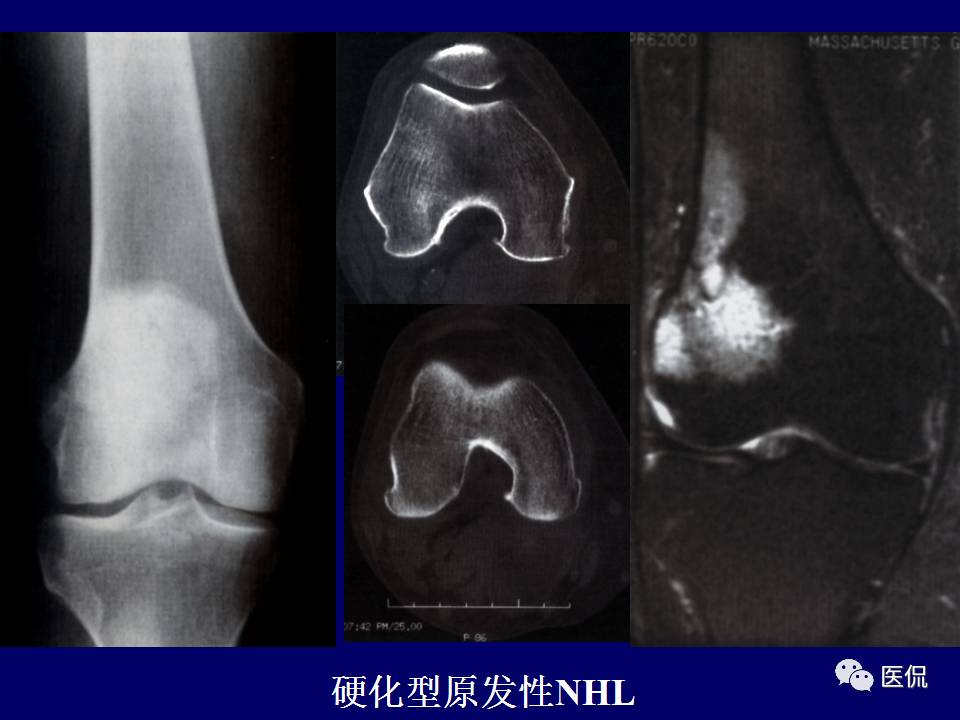

原发性骨淋巴瘤,是一种少见肿瘤。平片上干骺端单发、浸润性骨质破坏、层状骨膜反应+MR上骨髓侵犯、软组织肿块+年龄>30岁均可高度提示,影像学区分原发和继发PBL比较困难。更多知识,请往下看~